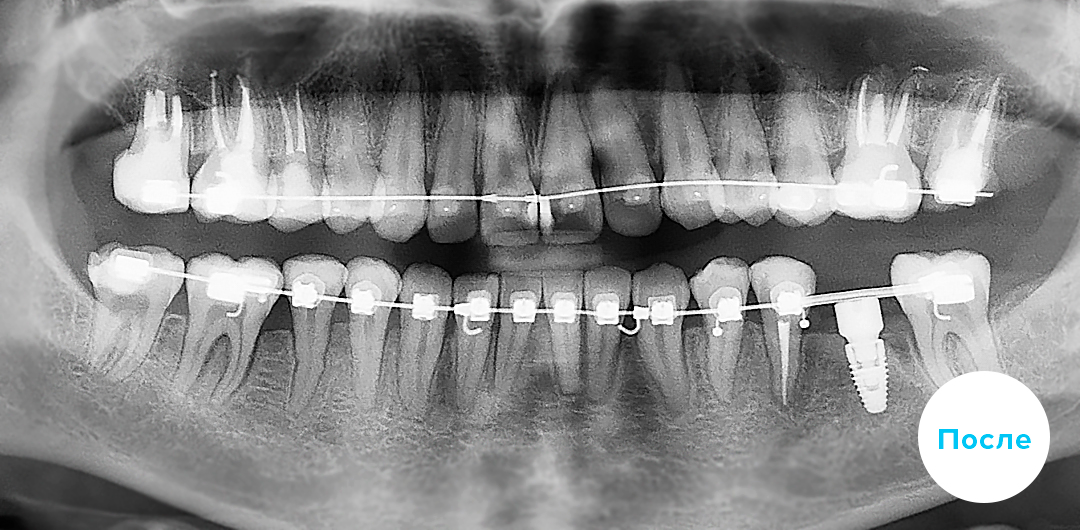

Индивидуальная брекет-система INSIGNIA (Инсигния) — это уникальная цифровая система от Ormco. Она моделируется при помощи CAD/CAM технологий на базе самолигирующих брекетов Damon. Эта опция возможна для двух разновидностей таких брекетов: керамических Damon Clear и металлических Damon Q. Изготавливаются индивидуально для каждого пациента по его “мерке” при этом, каждый брекет может быть как уникален, так и выбран из имеющейся серийной линейки. Компьютерное моделирование процесса ортодонтического лечения позволяет добиться прогнозированного и безукоризненно точного исправления прикуса и выравнивания зубов. Внешний вид системы INSIGNIA не отличается от обычных брекетов Damon – керамических или металлических, как и стоимость лечения на такой системе в клинике «Полный порядок».